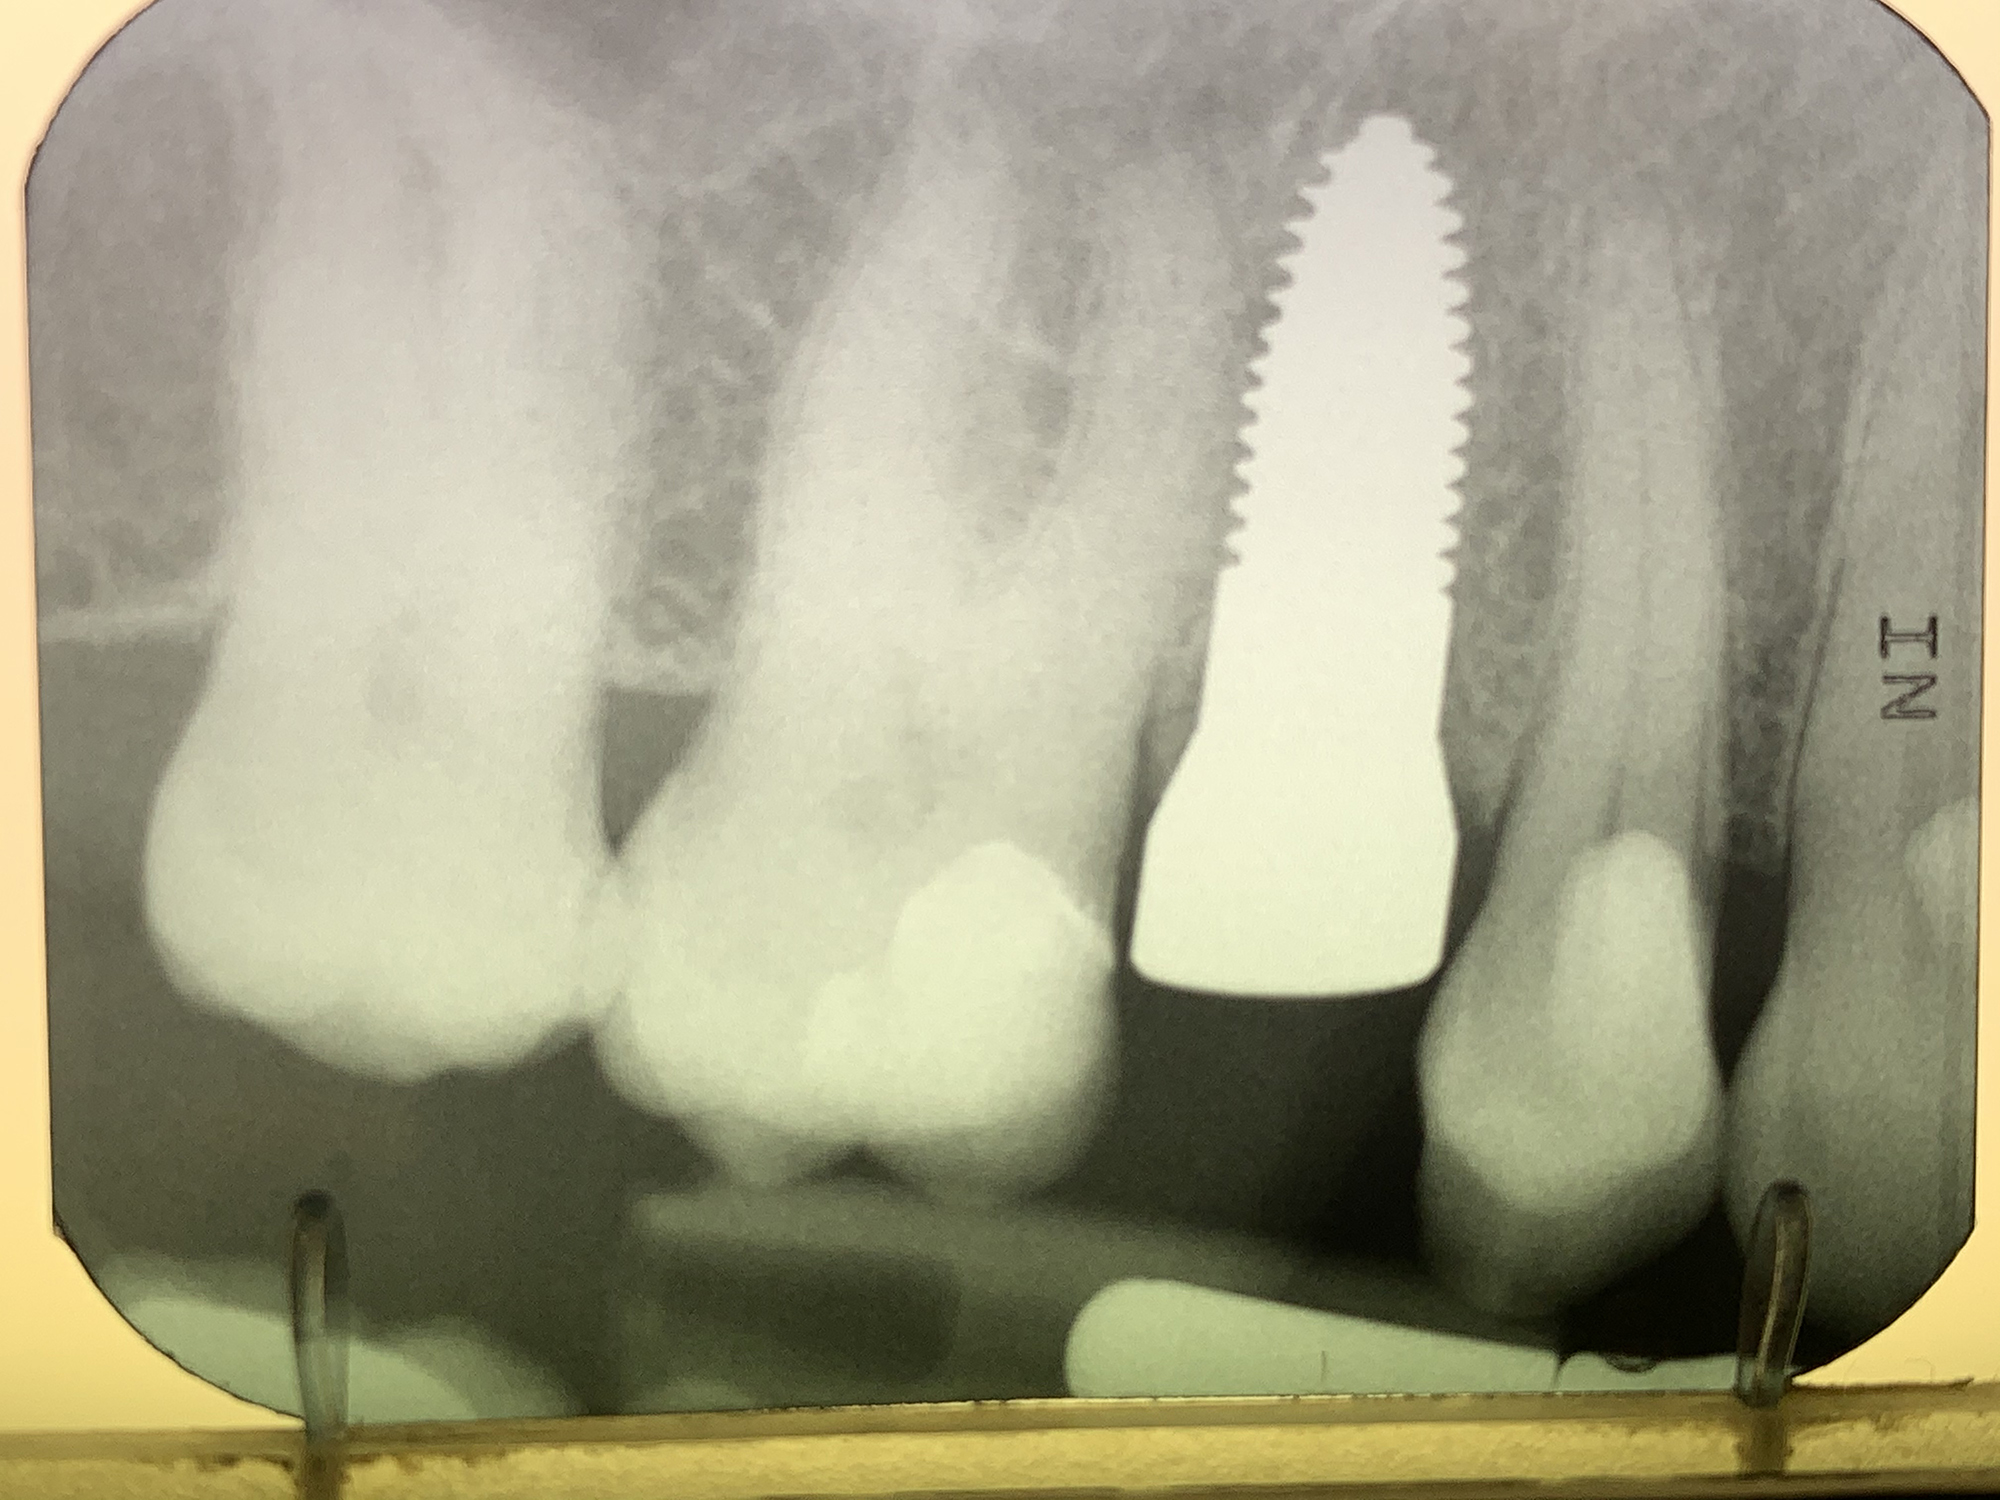

Überzeugende Vorteile von SDS Keramik-Implantaten

• SDS Keramik-Implantate sind absolut biokompatibel, damit sehr gut verträglich und heilen fest in den Knochen ein (Osseointegration)

• Die langfristige Haltbarkeit ist unbegrenzt und liegt nach aktuellem Wissen höher als die von natürlichen Zähnen

• Dank des einzigartigen Implantat-Designs des Marktführers SDS SWISS DENTAL SOLUTIONS ist in den meisten Fällen das Setzen der Implantate direkt im Anschluss an die Extraktion und somit in nur einem Eingriff möglich. In diesen Fällen kann meist auch gleich ein neuer provisorischer Zahn aufgesetzt werden

• Das Risiko einer Periimplantitis (chronische, schmerzhafte Entzündung des Zahnfleisches um ein Implantat herum), ist bei Implantaten aus Keramik praktisch nicht gegeben